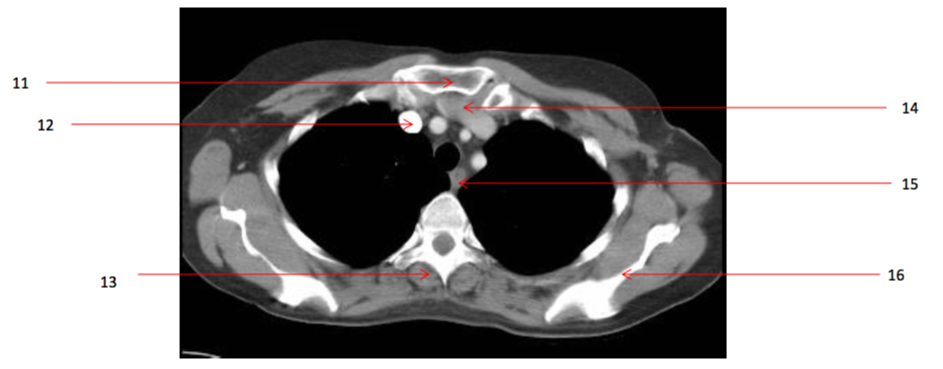

17

Number 11?

Sternum (manubrium)

15

Number 14?

Lt brachiocephalic vein

16

Number 17?

SVC

20

Number 12?

Rt brachiocephalic vein

10

Number 13?

Rt erectae spinae muscle

13

Number 16?

Lt scapula

43

Number 15?

oesophagus